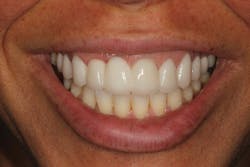

• site development to increase hard and soft tissue for pontic sites in fixed bridge prosthetics (figures 9–14);• correcting bone defects impinging upon anatomical structures after tooth extraction, such as oroantral communication (figure 18); and